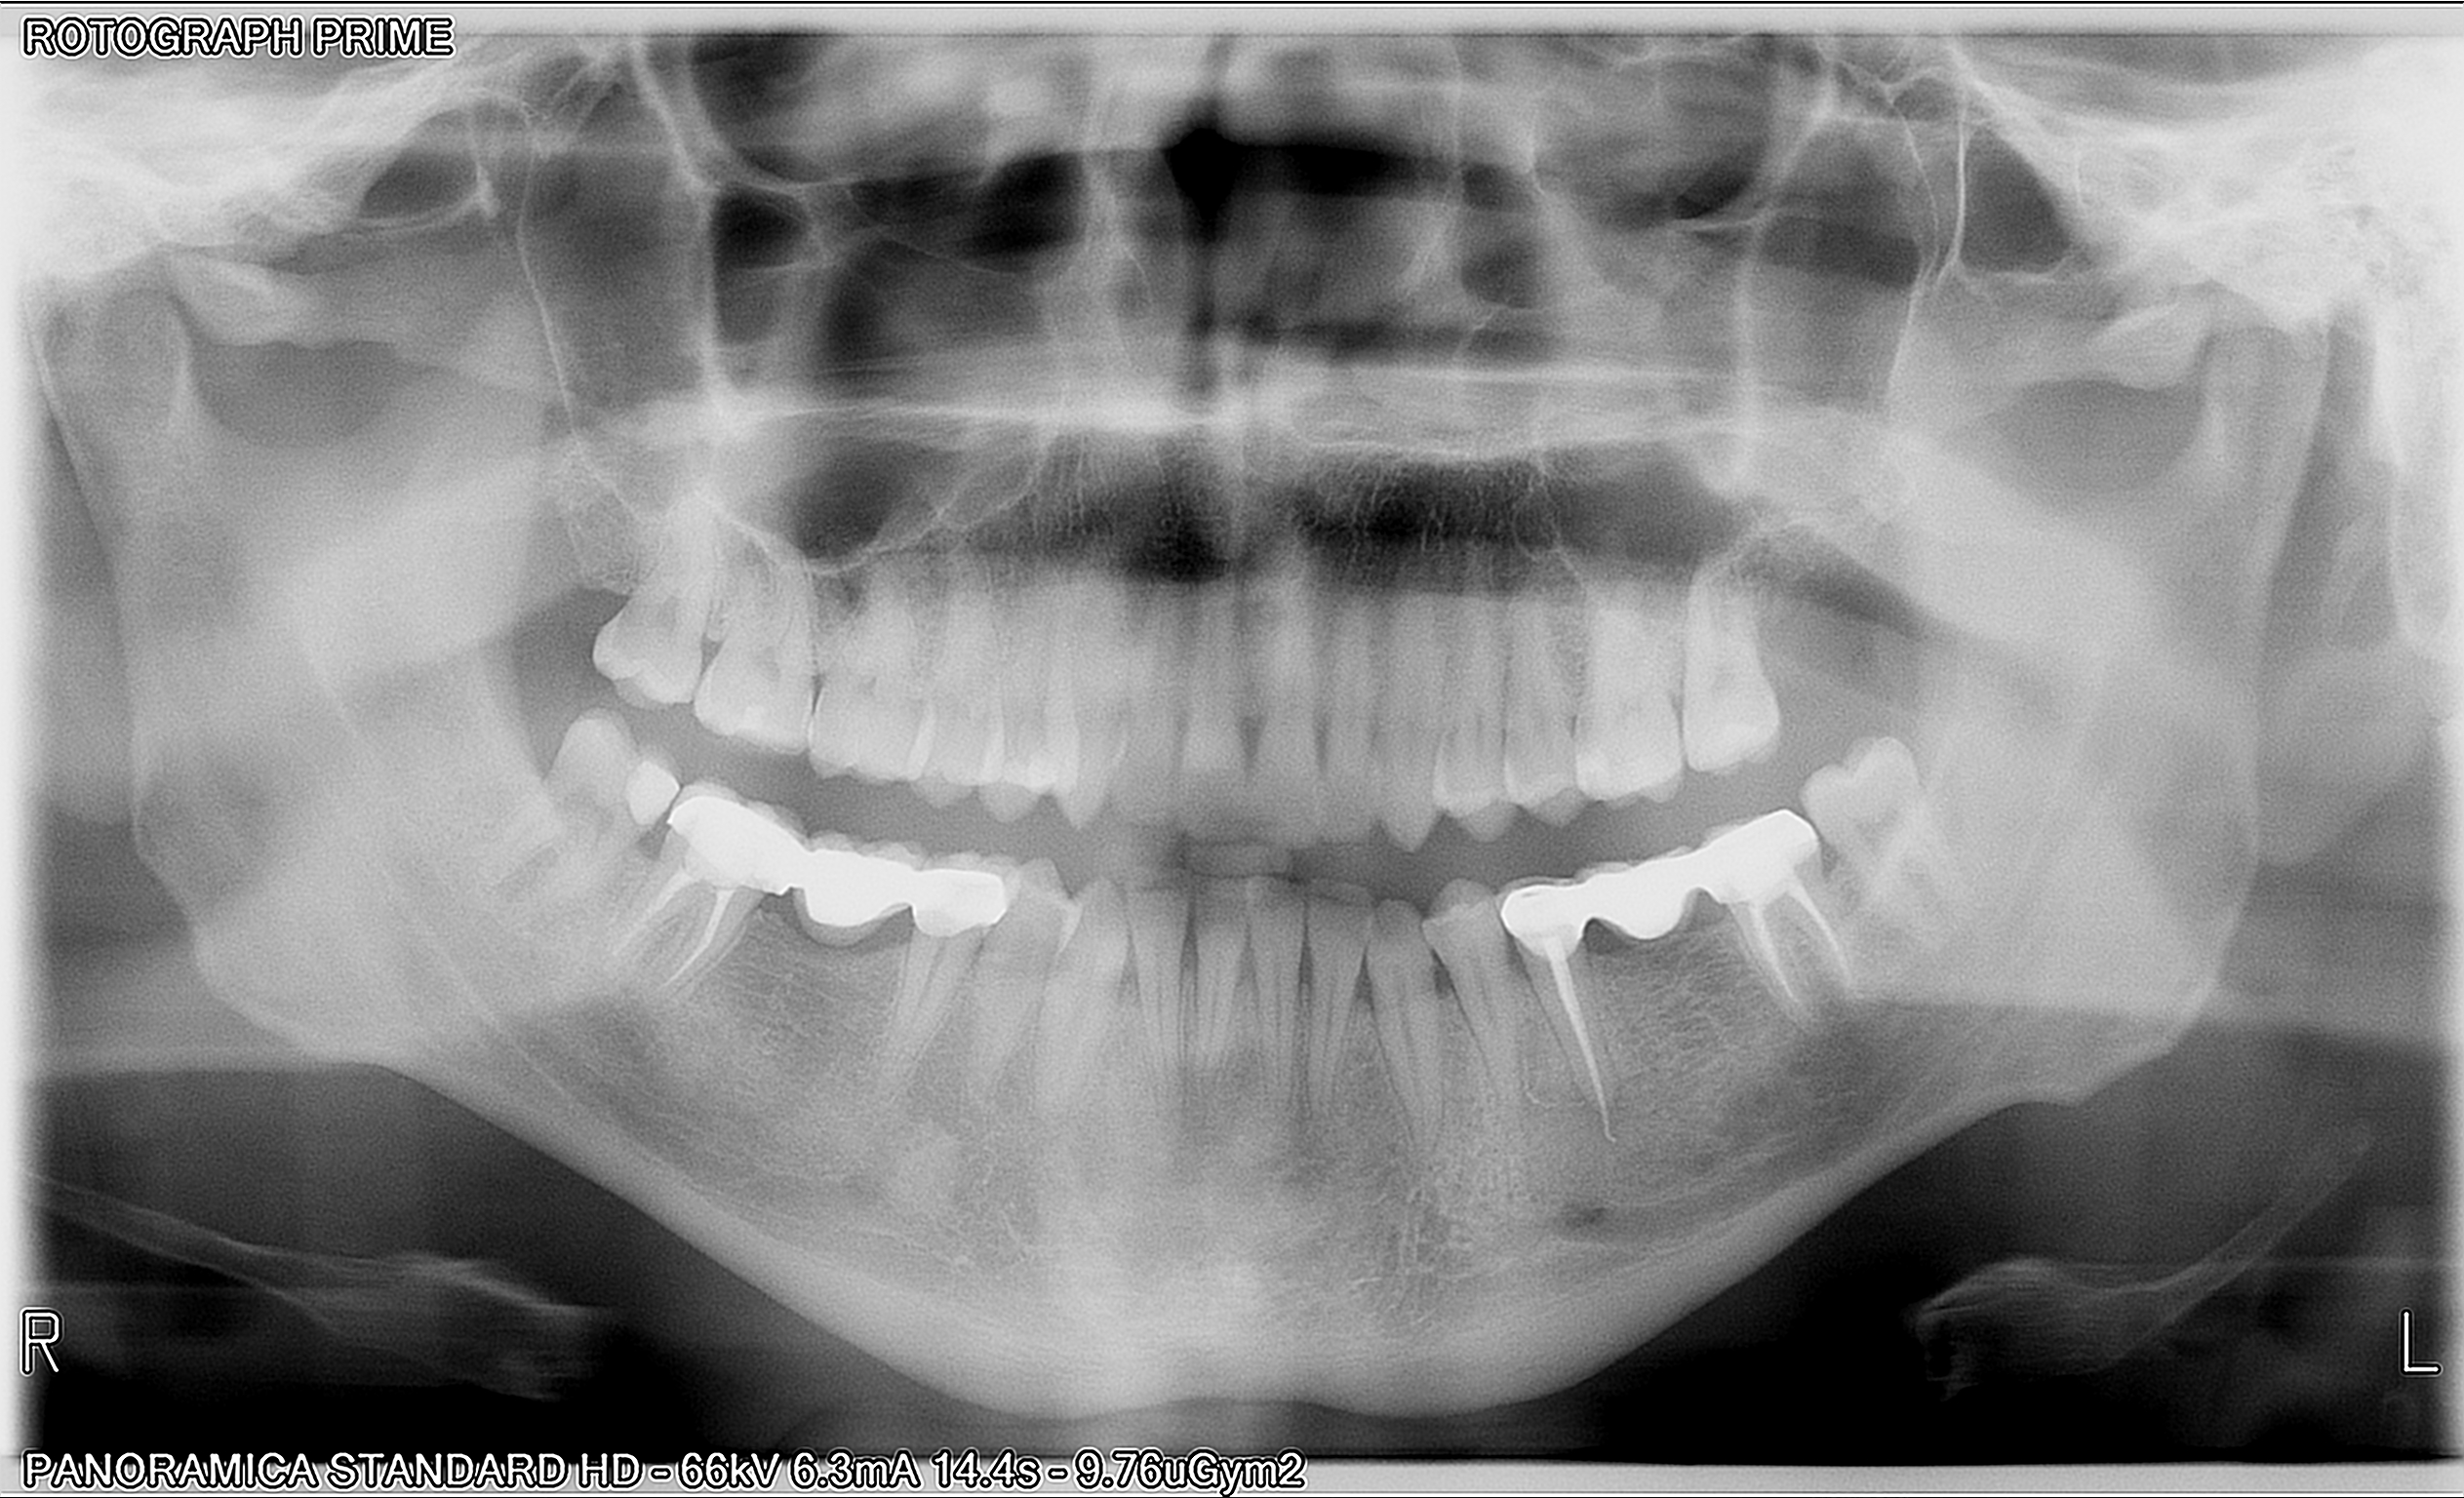

Egregi Dottori, siccome circa 4 mesi fa mi trovavo all'estero per lavoro e mi era apparsa una pallina bianca non dolorosa accanto ad un premolare (il 35, come vedete dalla prima foto) mi rivolsi ad un dentista del posto che mi fece fare un'ortopanoramica dalla quale risultò il sospetto di un granuloma periapicale del 35 (area ombreggiata rotonda della prima rx). Il dentista provò a curarmi il granuloma effettuando un forellino sul premolare evitando così di togliere il ponte di tre elementi che avevo. Dopo pochi giorni la pallina bianca però ricomparve e il dentista effettuò di nuovo la cura canalare su quel dente. Credo che quel dente fosse già devitalizzato da prima (credo da circa sette anni, quando feci il ponte). Poi feci altri lavori da quel dentista (rimozione di altre carie, rimozione di un dente del giudizio cariato, devitalizzazione del 37 per dei dolori che avvertivo sotto al ponte ecc...). Insomma, il problema della pallina sembrò risolto per un pò ma alla fine di maggio 2019 mi ricomparve di nuovo la pallina bianca accanto a quel premolare, anche se questa volta più piccola. Inoltre, ogni tanto sento come dei fastidi sotto al dente o al ponte, che non sono dolorosi ma soltanto una specie di formicolii o come se scavasse qualcosa sotto (tipo un tarlo). Nel frattempo, trovandomi in Italia, mi sono rivolto al dentista di fiducia del mio paese il quale mi ha ordinato di rifare l'ortopanoramica, cosa che rifeci subito tre giorni fa. Costui, dopo aver posto a confronto la vecchia e la nuova rx (che qui vi allego entrambe), ha notato che sotto al dente 35 c'è ora un eccesso di guttaperca (quel filamento bianco nella nuova rx scende troppo sotto) e secondo lui la ricomparsa della pallina e i leggeri fastidi che provo sono dovuti a questo eccesso di guttaperca. Lui dice che andrebbe rifatta di nuovo la cura canalare su quell'area ma potrebbe non riuscire e inoltre mi ha detto che lui non può farla perché servono strumenti appositi che vanno in profondità e che nel suo studio dentistico non ha. Io a questo punto non so cosa fare e per questo chiedo vostre opinioni in merito: è rischioso far restare quella guttaperca in eccesso? Potrebbe portarmi complicanze (ingresso di batteri, infezioni, altri rischi, ecc...)? Quella pallina che mi è ricomparsa anche se più piccola potrebbe essere sintomo di qualcosa? Dalla nuova rx si può capire se il granuloma sta ricomparendo in quel punto? E soprattutto, voi mi consigliate di farla rimuovere oppure no la guttaperca in eccesso da un altro dentista che abbia gli strumenti? Allego foto delle due rx, e foto della prima pallina (grande) e recente pallina (più piccola) spuntatami. Vi ringrazio in anticipo per il vostro aiuto e per i vostri chiarimenti

Il problema non è l'eccesso di guttaperca, forse vi siete capito male con il collega, ma probabilmente, nonostante la cura canalare sembri eseguita correttamente, manca il sigillo apicale, dato che appunto rimane la presenza della fistola.

L'elemento deve essere ritrattato per via ortograda e se l'intervento non ha successo, si deve procedere chirurgicamente per via retrograda, ed il problema si risolve.

Non è l'eccesso di guttaperca a creare questa lesione ma la patologia infettiva no completamente eliminata. Spesso vi sono nei denti dei canali accessori apicali infetti. L'unico modo per eliminarli è l'apicectomia. Le consiglio anche di curare di più la sua igiene orale.